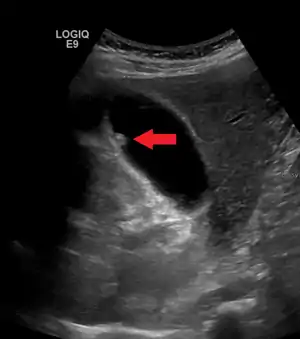

Adenomyomatosis describes a diseased state of the gallbladder in which the gallbladder wall is excessively thick, due to proliferation of subsurface cellular layer. It is characterized by deep folds into the muscularis propria. Ultrasonography may reveal the thickened gallbladder wall with intramural diverticulae, called Rokitansky-Aschoff sinuses.[3]

Ultrasound image of gallbladder polyps measuring 3–7 mm.